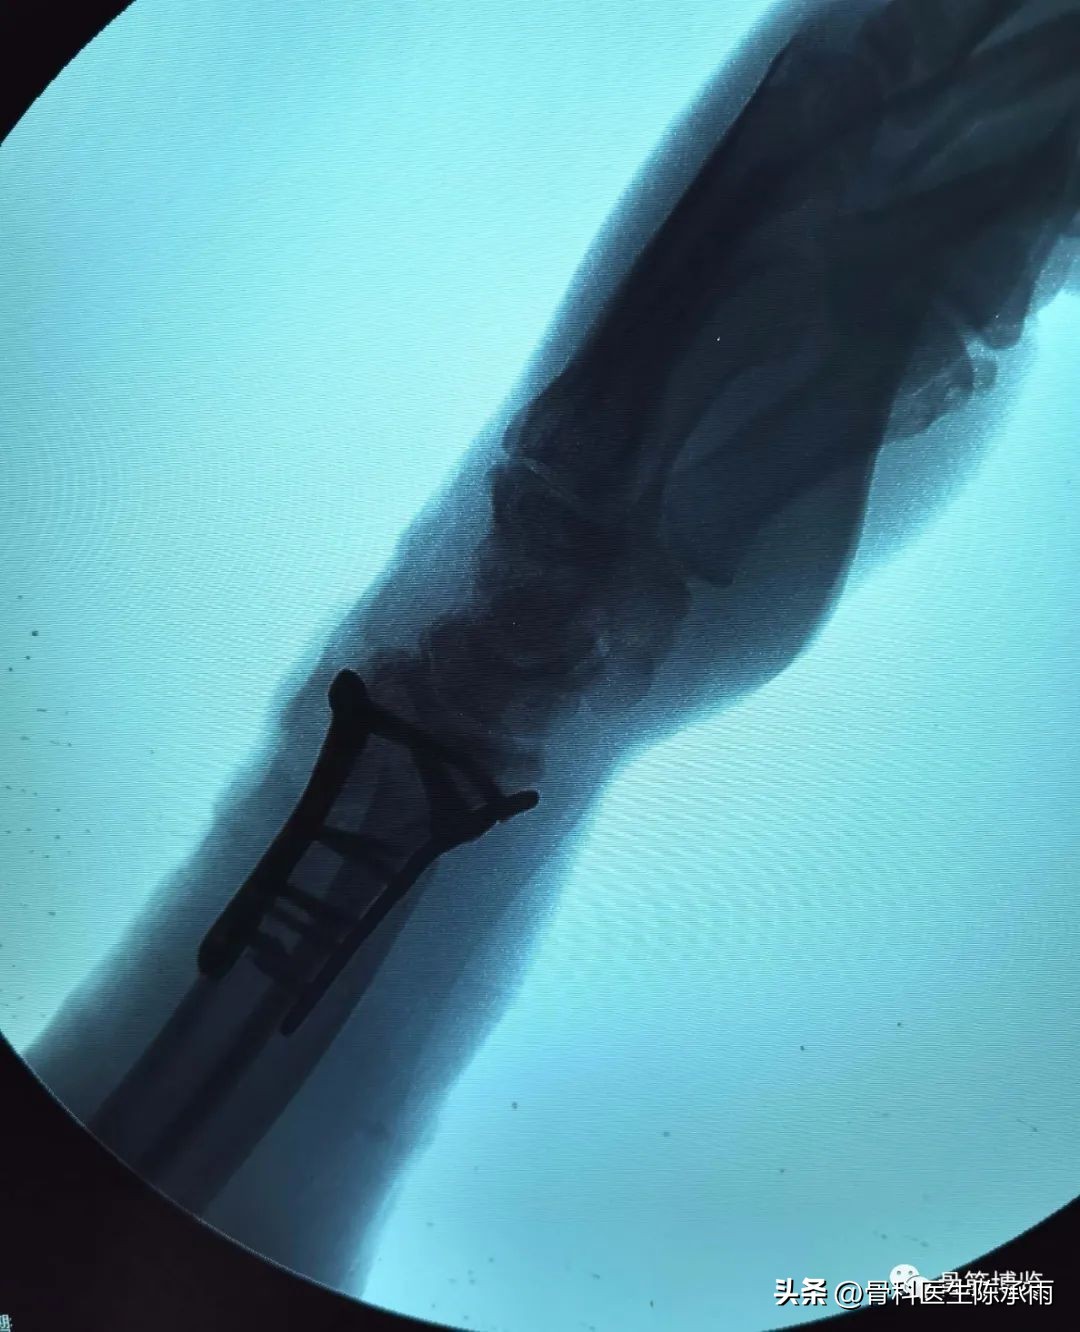

术中C臂